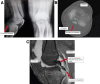

This study describes a method of fixing posterior cruciate ligament (PCL) avulsion fractures called the arthroscopic crisscross technique. PCL avulsion fracture is a rare injury that generally occurs in young patients. A displaced avulsion fracture at the tibial attachment of the PCL is an indication for surgical reduction and internal fixation given that nonunion, posterior instability, and early degenerative changes of the knee are common consequences of conservative treatment. This study describes all-arthroscopic fixation of the PCL avulsion injury using 2 No. 2 FiberTape sutures (nonabsorbable polyblend; Arthrex) via the arthroscopic crisscross technique. The No. 2 FiberTapes crisscross each other over the avulsed fragment. Through tensioning of both No. 2 FiberTapes, they are fixed anteriorly using a suture button. This technique can be considered a safe and effective method using minimal resources for the fixation of the avulsed PCL from its tibial footprint.